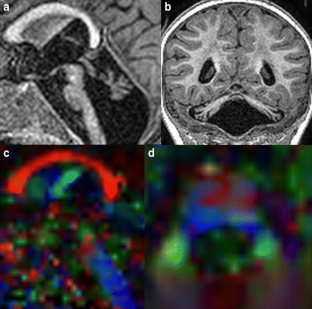

Fig. 1